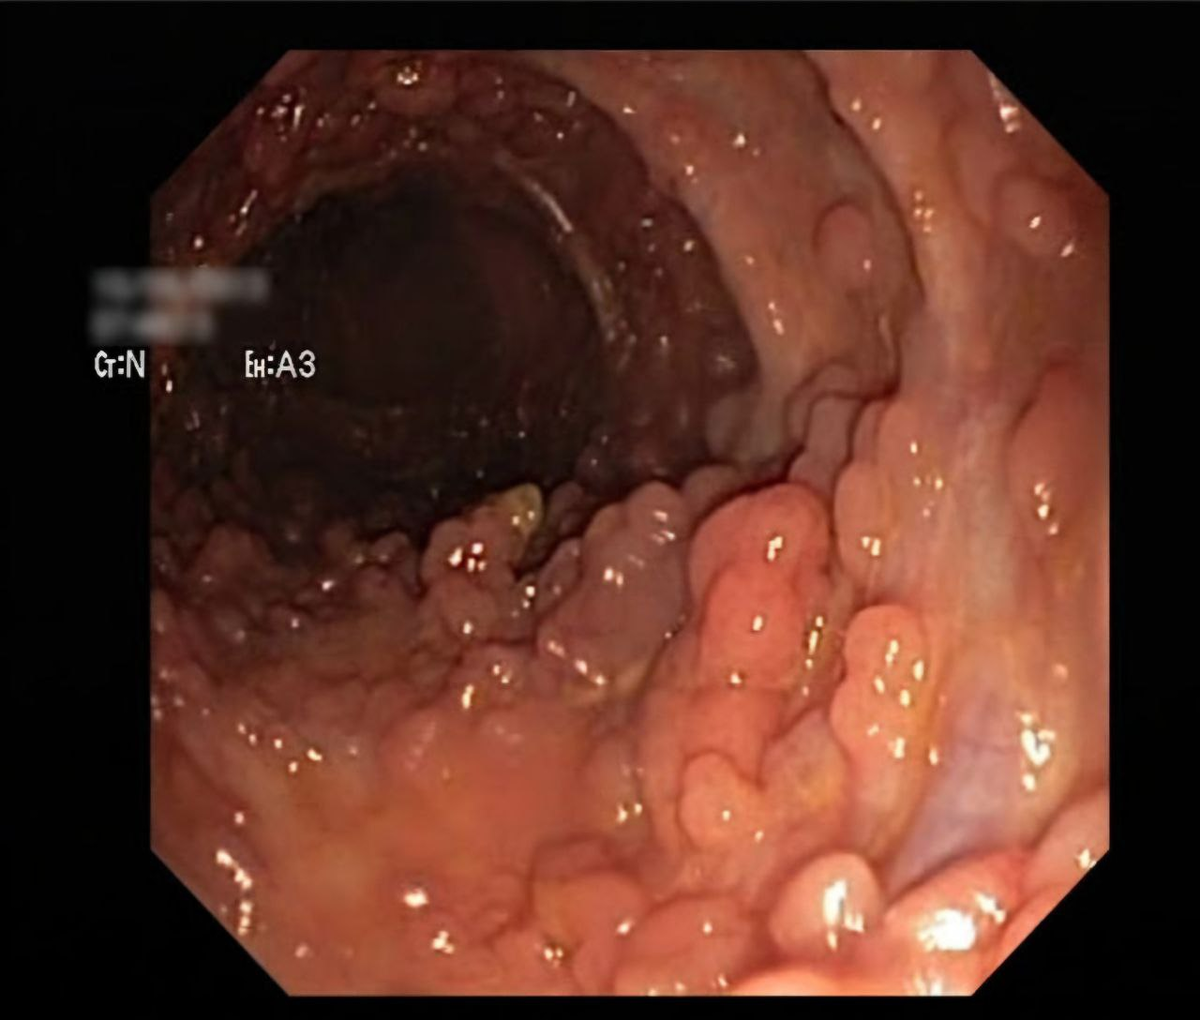

Семейный аденоматоз толстой кишки

Семейный аденоматоз толстой кишки является наследственным заболеванием, характеризующимся развитием в толстой кишке, а также различных отделах желудочно-кишечного тракта, множества полипов с чрезвычайно высоким риском их злокачественной трансформации.